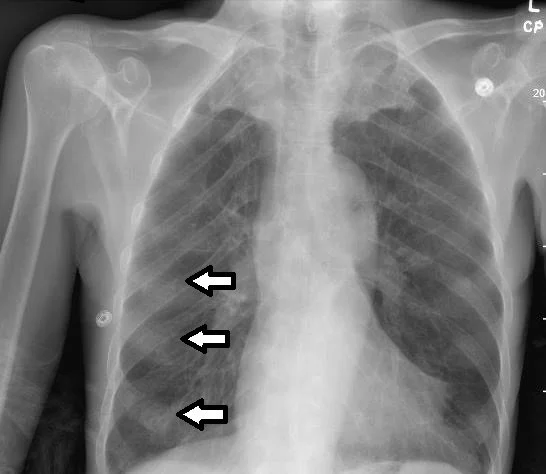

A 65 y.o. quadriparetic male fell and comes to the ED for evaluation

What do you see on his cxr?

What are those nodules?

Our patient had Vit D deficiency and had developed a rachitic rosary;  a series of enlargements at the costochondral junctions of the anterior ribs.

Lack of vitamin D causes decreased calcium absorption in the gut and this causes a lack of mineralization and overgrowth of the cartilage at the joints.  Scurvy can also cause a scorbutic rosary because vit C deficiency causes abnormalities of bone growth and periosteal elevation.

The differential would also include diseases of impaired bone growth or marrow expansion. Paget’s disease, fibrous dysplasia and thalassemia are included.